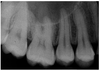

This is an air-containing cavity in maxilla, margins are made by a thin layer of dense bone

maxillary sinus

The anterior border of the maxillary sinus often intersects a line formed by what

floor of nasal fossa

maxillary sinus involving roots of maxillary premolars and molars